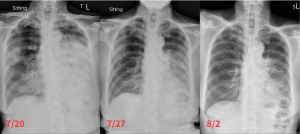

居住在臺東的七十一歲方奶奶因常咳不癒且有大量痰液,疑似難治型肺炎,在當地住院治療一個月,病情無絲毫起色,於二○二三年七月下旬轉往花蓮慈濟醫院。胸腔內科主任林智斌醫師問診後,懷疑病人的疾病並不單純,經切片檢驗結果確為肺腺癌,隨即以標靶藥物治療。目前病人已恢復穩定,返家休養。